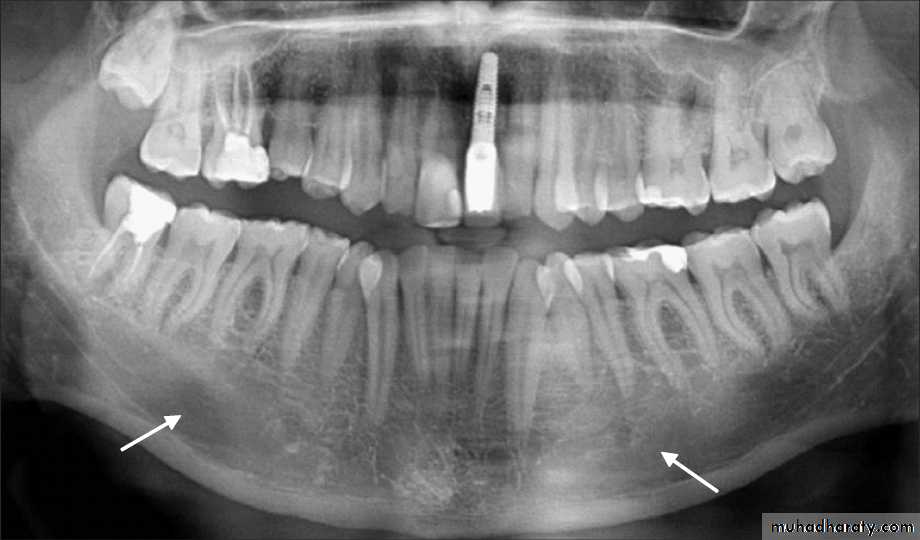

Cortical bone varies in thickness in different areas – it is thicker in the mandible than in the maxilla and thicker in the premolar-molar region than in the anteriors.

Type I: the trabaculae are regular and horizontal. This is seen most commonly in the mandible.

Type II: irregularly arranged delicate and numerous trabaculae. This is seen most commonly in the maxilla.

The spongy bone is very thin or absent in the anterior regions of both the jaws.